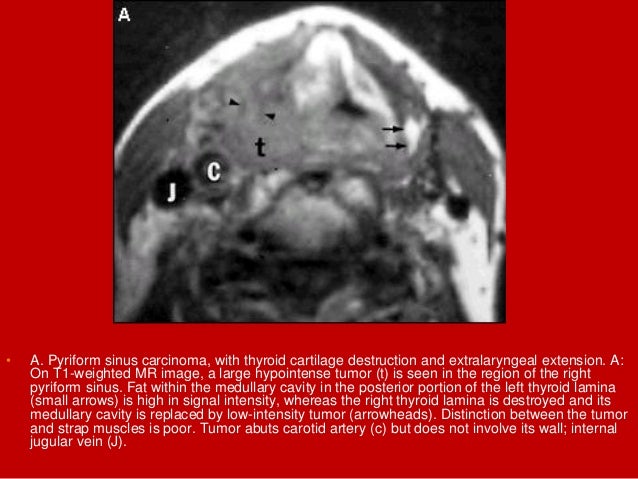

67. 67. • A. Pyriform sinus carcinoma, with thyroid cartilage destruction and extralaryngeal extension. A: On T1-weighted MR image, a large hypointense tumor (t) is seen in the region of the right pyriform sinus. Fat within the medullary cavity in the posterior portion of the left thyroid lamina (small arrows) is high in signal intensity, whereas the right thyroid lamina is destroyed and its medullary cavity is replaced by low-intensity tumor (arrowheads). Distinction between the tumor and strap muscles is poor. Tumor abuts carotid artery (c) but does not involve its wall; internal jugular vein (J).

68. 68. • B. Pyriform sinus carcinoma, with thyroid cartilage destruction and extralaryngeal extension. B: On T2-weighted image, the extralaryngeal extension of hyperintense tumor (large arrow) and the strap muscles (S) are better delineated. Contrast between the tumor and fat within the paralaryngeal space is decreased. C, carotid artery; J, jugular vein; SCM, sternocleidomastoid muscle.